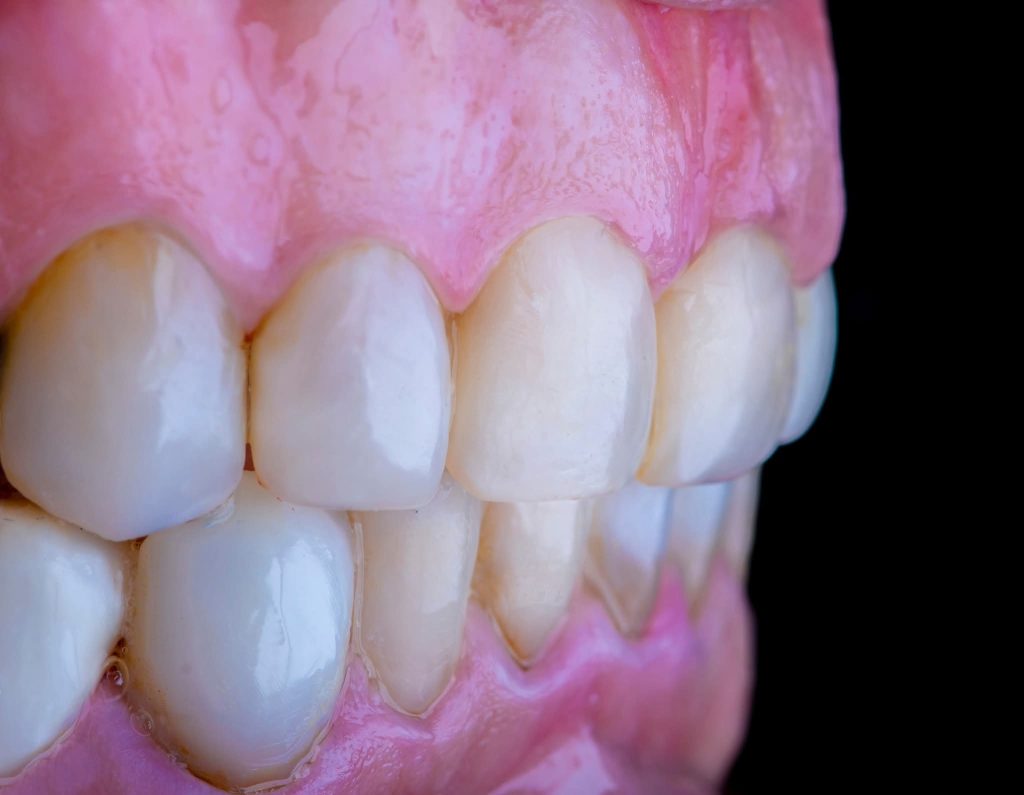

The case was transferred to a semi-adjustable articulator, where the vertical dimension was increased by 5 mm. A diagnostic wax-up and removable prostheses were created at the new vertical dimension, guided by the curve of Spee using Broadrick’s Occlusal Plane Analyzer. Silicone indices were fabricated for both arches.

3. Definitive Phase:

This phase began with the upper arch:

Placement of implants in the free-end areas.

Preparation of teeth and insertion of the fixed prosthesis.

The lower arch was managed similarly to the upper arch.